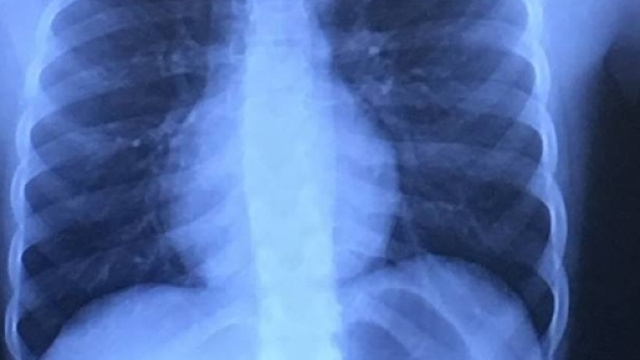

Trasportata in ambulanza al Texas Children's Hospital, la bambina è stata sottoposta ad una radiografia che ha permesso di localizzare il dischetto del gioco nell'esofago. Non c'è stato altro da fare che operarla d'urgenza per estrarre il pezzo del fidget spinner.